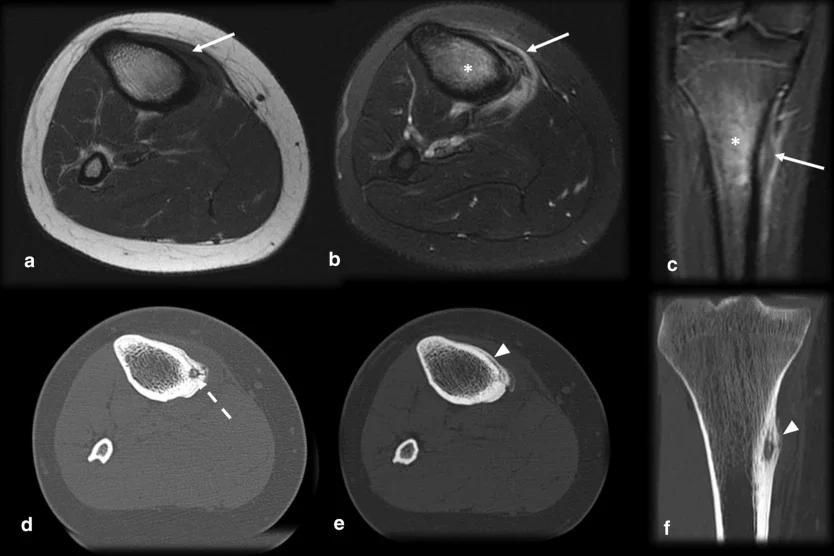

Изображение: Субхондрален остеоид остеом, имитиращ трохлеарна хондромалация. 35-годишен мъж с болка в предната част на коляното в продължение на 4 месеца. Аксиални T2 FS MR изображения (a), показващи дълбока хондрална ерозия (стрелка), субхондрален оток (звездичка) и малки огнища с нисък интензитет на сигнала, които биха могли да бъдат нидус (пунктирана стрелка). Сагитална T1 MRI (b) и CT (c) потвърждават диагнозата на остеод остеома нидус (пунктирана стрелка). Хирургични изображения преди (d) и след (e) резекция. Използвано от springermedizin.de под Creative Commons Attribution 4.0 International License.

Изображение: Остеоид остеом при 15-годишен футболист с постеромедиална болка в тибията в продължение на 3 месеца, която се влошава по време на тренировка и при палпация на горната постеромедиална тибия. ЯМР аксиален T1 ( ), аксиален (b) и коронален (c) T2 FS показва кортикално удебеляване, периостална реакция, оток на сухожилието на pes anserinus (стрелки) и оток на костен мозък (звездичка), имитиращи стрес фрактура. По-нататъшното изследване с компютърна томография (d,e,f ) показва огнище (пунктирана стрелка), причиняващо тази кортикопериостална реакция (връх на стрелка) и потвърждаващо остеоид остеома. Използвано от springermedizin.de под Creative Commons Attribution 4.0 International License.